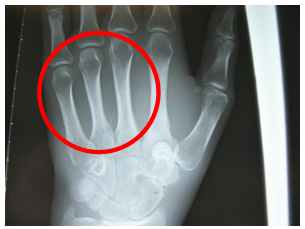

On examination there was a tenderness over the base of the second metacarpal bone and a slight swelling at the site of the tenderness with no skin changes (Figure 1) Other than this, the ROM, power of grip and sensation are within the normal level in comparison to the other normal side.

Figure 1